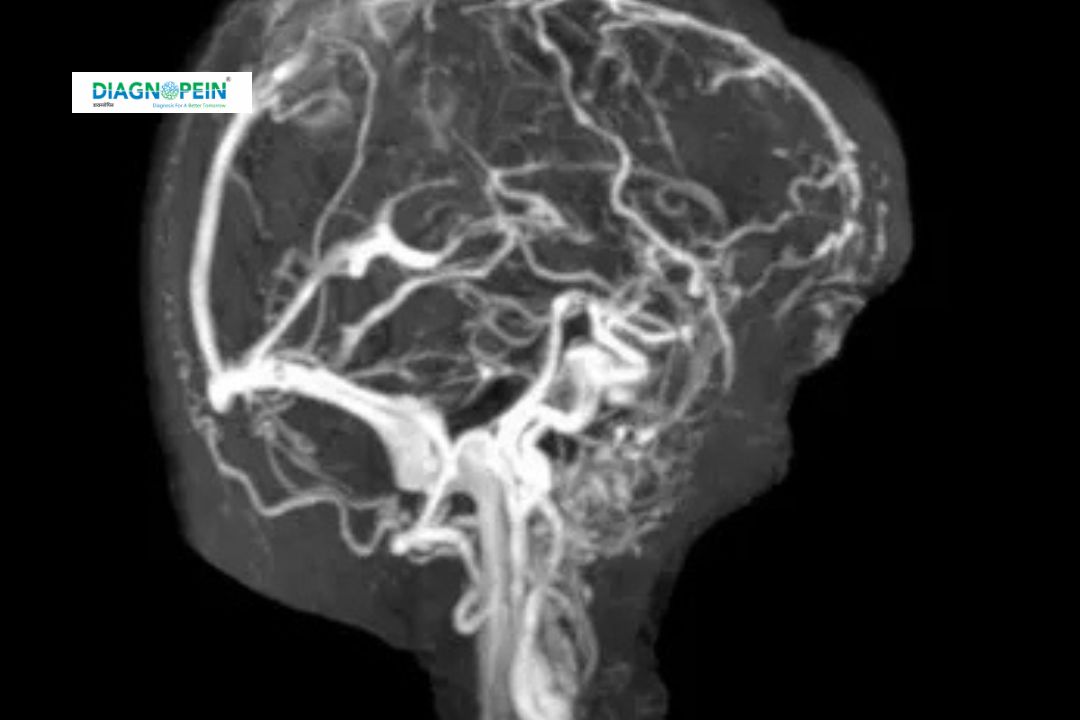

Diagnopein MRI Angiography - with contrast Centre in Nanded

MRI Angiography with contrast (MRA) is a sophisticated imaging technique using magnetic resonance imaging alongside a contrast dye, usually gadolinium-based, to closely examine blood vessels. It helps visualize arteries and veins to detect abnormalities such as aneurysms, blockages, or malformations. Unlike traditional angiography, MRA is non-invasive and does not expose patients to radiation, making it a safer option for vascular assessment.